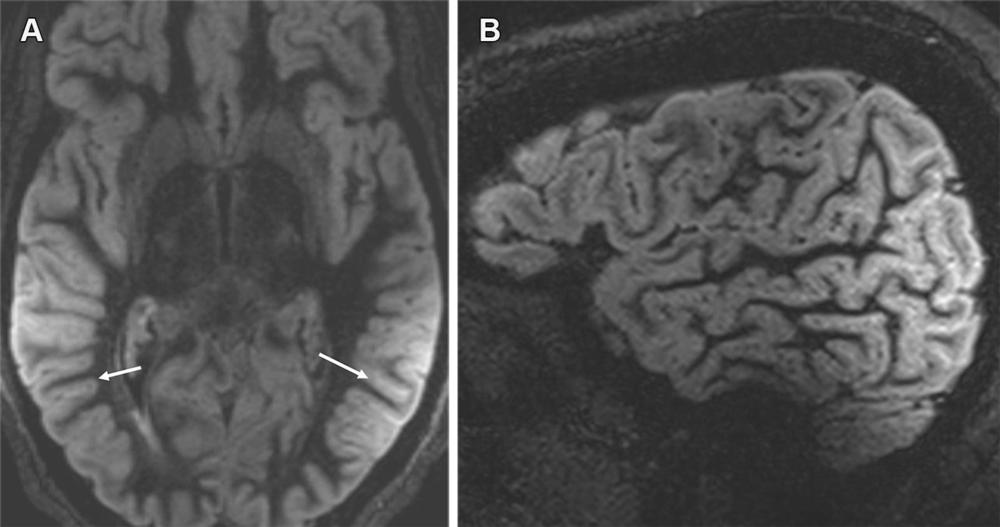

Figure 7. Severe ARIA-E (edema) in a 69-year-old woman receiving aducanumab therapy for AD with headaches and word-finding difficulty. (A, B) Axial MR images of the brain show multifocal subcortical edema (arrows) with FLAIR hyperintensity (A) and increased diffusion on the apparent diffusion coefficient (ADC) map (B), with a few areas measuring more than 10 cm. (C) Axial follow-up MR image 4 months later shows near-complete resolution of signal intensity changes. ARIA-E is most common in the occipital lobes (as in this case) and mimics posterior reversible encephalopathy syndrome (PRES) at imaging.

High-res (TIF) version